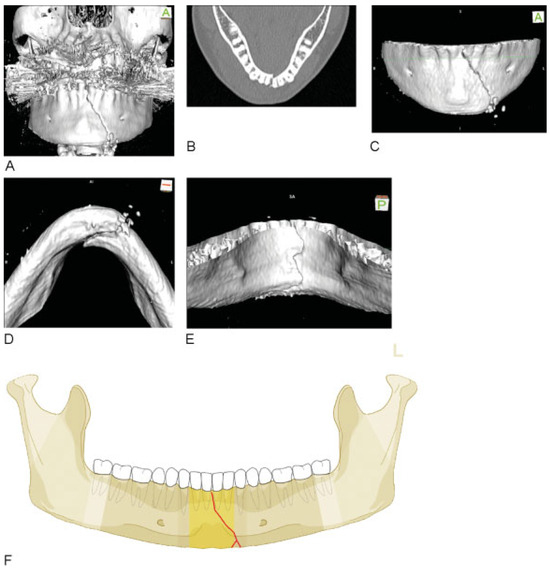

Figure 9.

Body fracture of grade 2 fragmentation extending into the symphysis. (A–D) Imaging: CT scans 3D reformatted overviews lateral, anterolateral, laterobasal, and lingual. Narrative description: A look from the outer surface shows multiple large-sized intermediate fragments confined to the mandibular body on the left in its full vertical height. The inspection of the inner aspect exhibits that the anterior tip of a large rhomboid intermediate fragment extends into the symphysis (below 32) (see shaded fragments in illustration below showing fracture pattern on lingual side, which is crucial for to code level 3). The fragmentation the body region is grade 2 and in the symphysis grade 1. (E) Code Level 3: 91 S1- B2. This case example CMTR-91-027 is made available electronically for viewing using the AOCOIAC software at www.aocmf.org/classification.